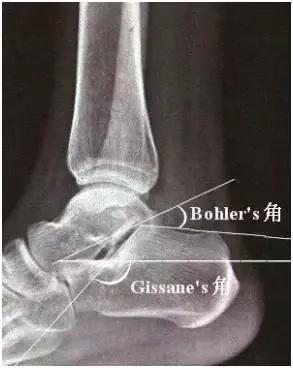

跟骨Bohler’s角的正常范围是20°到40°(考试必备的知识点),角度减小说明跟骨承重的后关节面塌陷,造成身体的重心相对前移,也有角度消失或反角的情况。Gissane’s角又叫“十字角”,它的正常范围是95°到105°,角度增大说明跟骨后关节面塌陷。